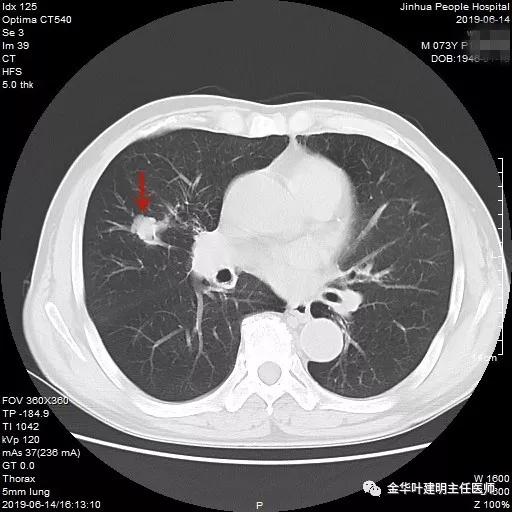

武义的吴某,今年已经73岁了,患有慢性支气管炎与肺气肿多年,每到天气转凉就要胸闷、气急及咳嗽、咳痰发作,严重时还有喘憋症状,每年都要住院1-2次。今年4月份的时候吴某又因慢支急性发作来我院呼吸内科住院。常规检查时发现右肺上叶有一实性结节,约1.5厘米大小,有毛刺及浅分叶,考虑肺癌可能性大,医生建议其行肺穿刺活检。当时图片如下: